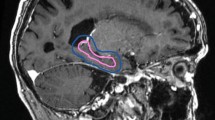

The dose parameters of Plan (AD) and Plan (MD) are listed in Table 2. Figure 5 presents the dose distribution of Plan (AD) and Plan (MD) for a case. For the hippocampus, the average Dmean was 906.9 ± 17.2 cGy in Plan (AD) and 898.8 ± 14.1 cGy in Plan (MD). Although the difference was statistically significant, it was not considered clinically significant. There are 6 cases in Plan (AD) which had a Dmax of the hippocampal exceeding 1600 cGy (range 1624.2–2196.2 cGy), the V16Gy of the hippocampus in these 6 cases ranged from 0.002 to 0.187%. For all the cases, Dmax of the hippocampal in Plan (MD) did not exceed 1600 cGy. For PTV and lens in these 11 cases, the differences were not statistically significant and all RT plans met the dose constraints.

Variations of dose distributions between plan (MD) and Plan (AD). a Plan (MD), b Plan (AD). Manually delineated hippocampus (yellow line), automatically delineated hippocampus (red line), and PTV (blue line). Radiotherapy plan generated by a manually and b automatically delineated hippocampus. Both plans were evaluated using the AD hippocampus. In Plan (AD), a small area of the manually delineated hippocampus received a dose of more than 1600 cGy